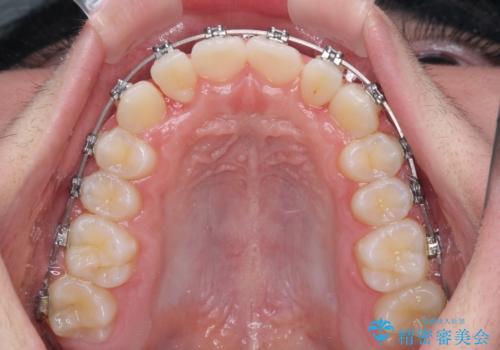

中学生のワイヤー矯正 クロスバイトを短期間で改善

- メタルブラケット

- 前歯のクロスバイトを気にして来院された患者様です。

中学生であることから、治療期間を短縮できると判断し、ワイヤー矯正にて短期間で治療を行うこととしました。

叢生のため磨き残しの多い歯列でしたが、1年弱で治療を終了でき、磨き残しや歯肉の腫れが著しく改善されました。